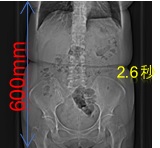

シーメンス社のテクノロジーにより、全身領域において高速スパイラルスキャンが可能です。

高速で230mm/秒で撮影することができ、例としておなか60cmの範囲を撮影するとした場合、約3秒の息止めで撮影することが可能です(検査の種類、目的により異なります)。